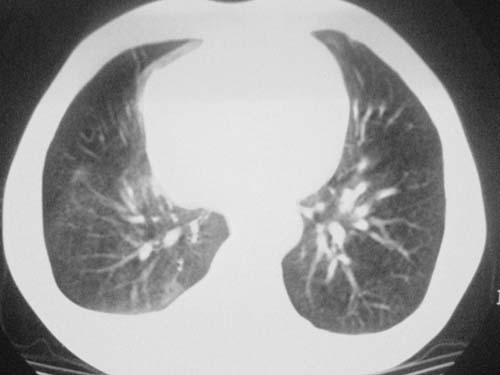

以下是引用科室第一人在2010-3-25 20:30:00的发言:[br]1:纵膈肿瘤性病变,恶性胸腺瘤可能性大伴纵膈右肺门淋巴结转移,右侧胸腔积液。[br]2:右侧肺门肿瘤性病变,纵膈淋巴结转移,右侧胸腔积液。右下叶转移。

以下是引用子期在2010-3-25 21:00:00的发言:[br]先考虑右中央型肺癌伴转移。

以下是引用江广1996在2010-3-25 22:49:00的发言:[br]通常肺癌向纵隔转移多见,纵隔肿瘤向肺内转移少见(有的表现为向肺内侵润)。本例以一元论考虑:右中心型肺癌并纵隔淋巴等多处转移。[br][br][本贴已被 江广1996 于 2010-3-25 22:50:07 修改过]

以下是引用yangyudong333在2010-3-26 6:43:00的发言:[br]“冰冻纵膈”,考虑纵膈淋巴瘤伴肺内及胸膜侵润。